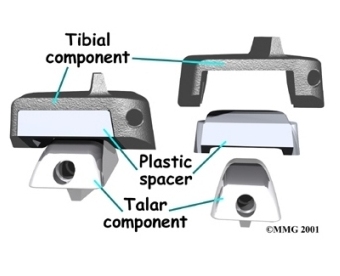

Each artificial ankle prosthesis is made of two parts:

- The tibial component is the part of the artificial joint that replaces the socket portion of the ankle (the top section).

- The talus component replaces the top of the talus.

The tibial component is usually made up of two parts: a flat metal piece called a metal tray that is attached directly to the tibia bone, and a plastic cup that fits onto the metal piece, forming a socket for the artificial ankle joint. The talus component is made of metal and fits into the socket of the tibial component.

Your surgeon may use a special type of epoxy cement to attach the metal components to the bone. This is called a .

Some surgeons prefer to put the new joint in without using cement. This is called an . The surface of this type of prosthesis bears a fine mesh of holes that allow bone to grow into the mesh and attach the prosthesis to the bone.